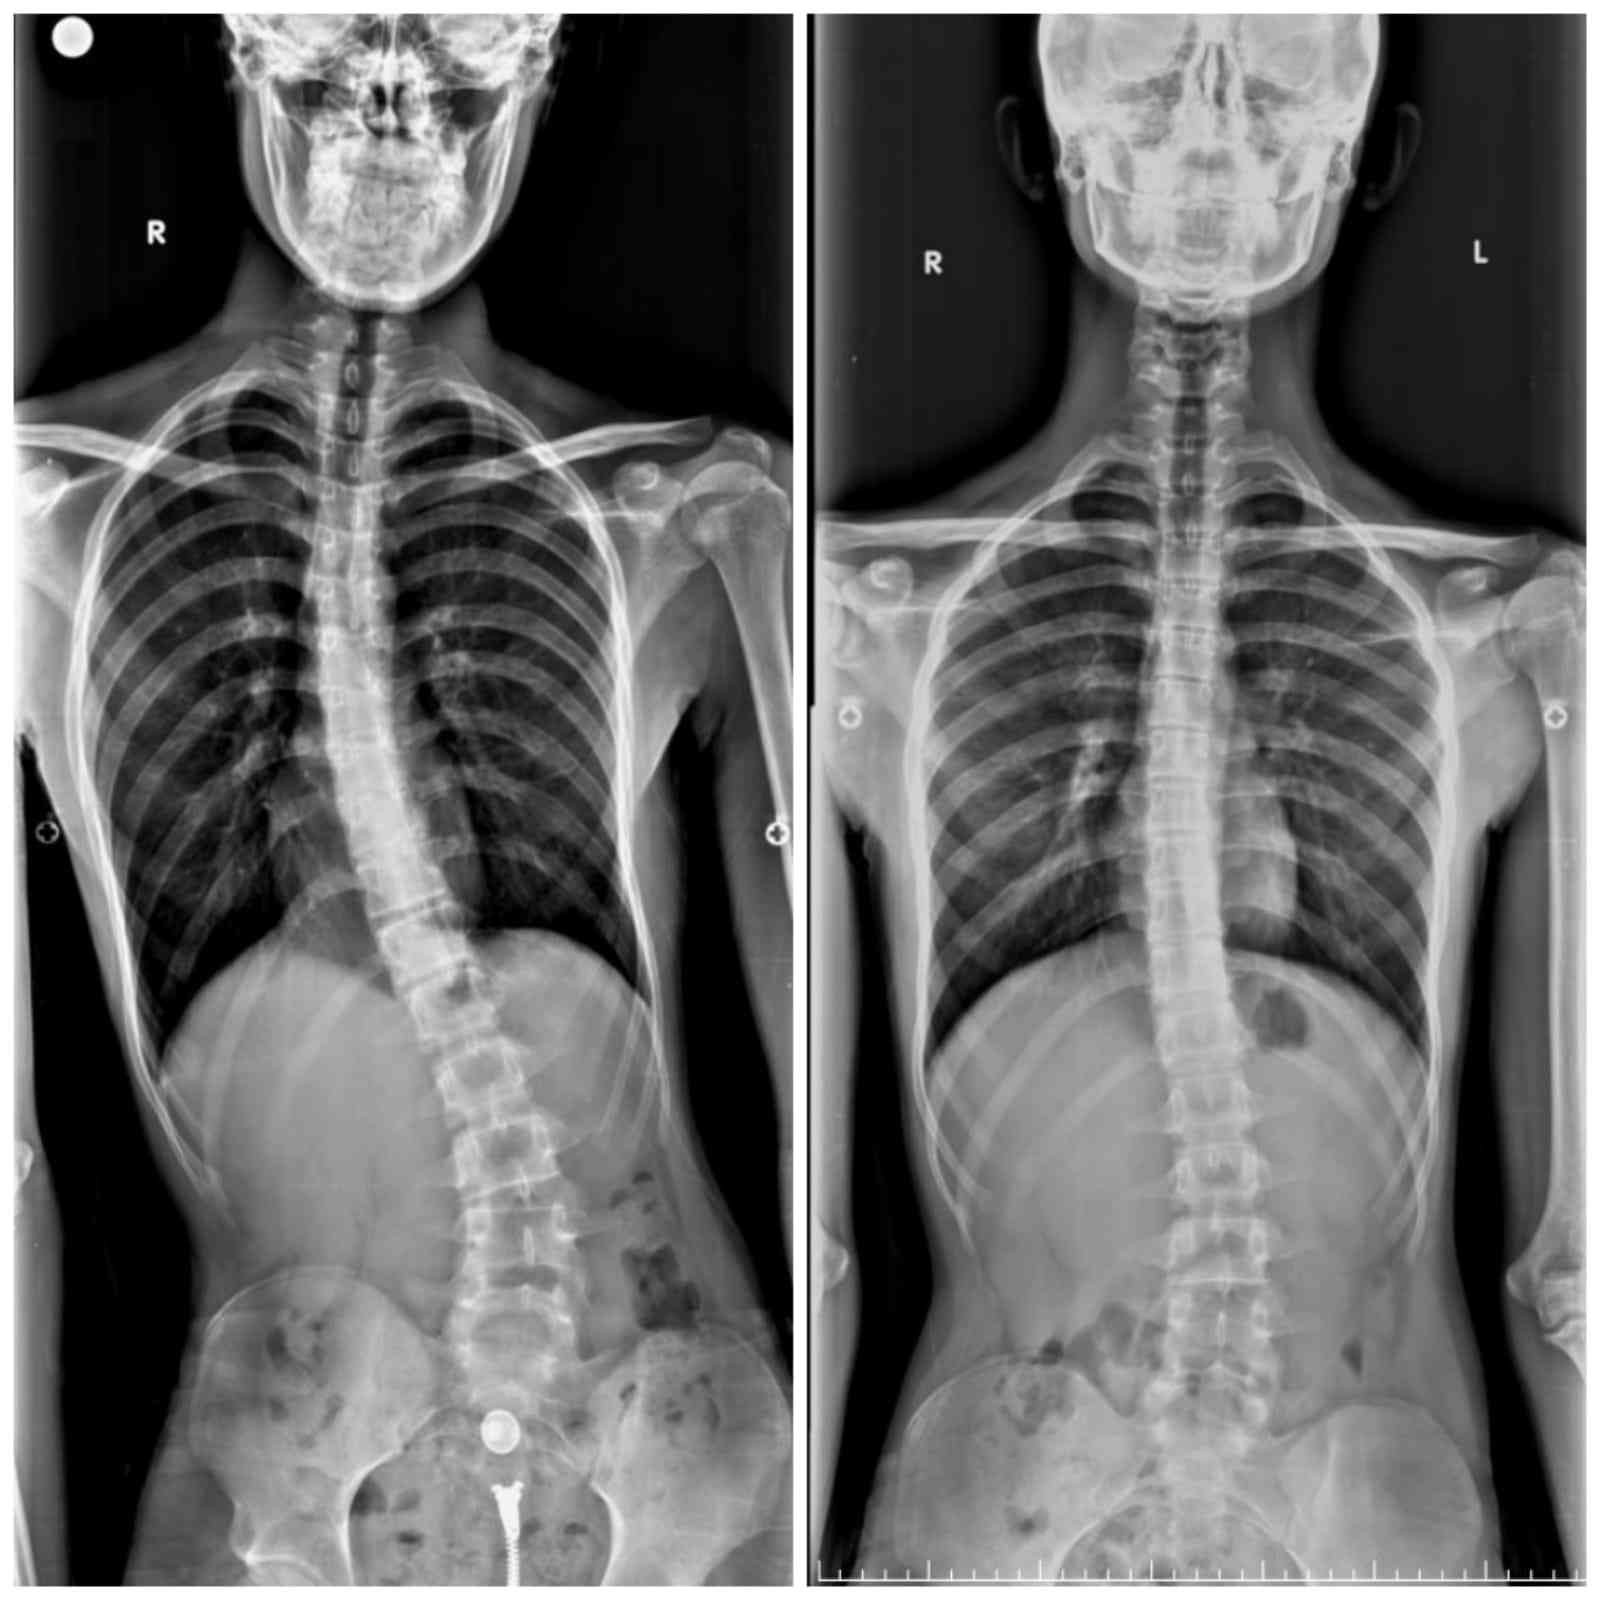

Adapazarı ilçesinde yaşayan 16 yaşındaki Aziz Koray Diş, 2021 yılının kasım ayında dengesini kaybederek bisikletten düşüp yaralandı. Geçirdiği hafif kaza sonrasında hastaneye gitmeyen Aziz Koray Diş, düştükten sonra vücudunda oluşan yaralara bakmak için aynanın karşısına geçince şok oldu. Vücudundaki eğriliği fark ederek annesine söyleyen ve sonrasında hastane hastane gezen Aziz Koray Diş’e bir türlü doğru teşhis konulamadı. Umudunu kaybetmek üzere olan genç, son olarak Sakarya Eğitim ve Araştırma Hastanesi’nde görev yapan Doç. Dr. Alauddin Kochai’ye başvurdu. Doç. Dr. Alauddin Kochai’nin yaptığı muayene sonrasında tüm tetkikleri yeniden yapılan 16 yaşındaki Aziz Koray Diş’e Osteoid Osteoma ismi verilen kemiğin iyi huylu tümörü teşhisi konuldu. Yapılan ilk tetkiklerin ardından 25 gün boyunca hastanede kalan Aziz Koray Diş, burada ameliyat için hazırlandı.

Aziz Koray Diş’in sosyal hayatını da etkileyecek dereceye gelen eğriliğinin tespiti sonrasında hızlıca tedavi sürecine geçildiğini belirten Sakarya Eğitim ve Araştırma Hastanesi Ortopedi ve Travmatoloji Bölümü’nde görevli Doç. Dr. Alauddin Kochai, “Aziz’in bize geldiğinde ciddi bir eğriliği vardı ve bu eğriliğin kaynağı bir türlü bulunamamıştı. Burada gerekli tetkikleri yaparak bu eğriliğin iyi huylu tümör olduğunu belirledik ve buna yönelik yaptığımız cerrahi sonrasında sağlığına kavuştu ve 2 ay içerisinde tamamen sağlığına kavuştu” dedi.